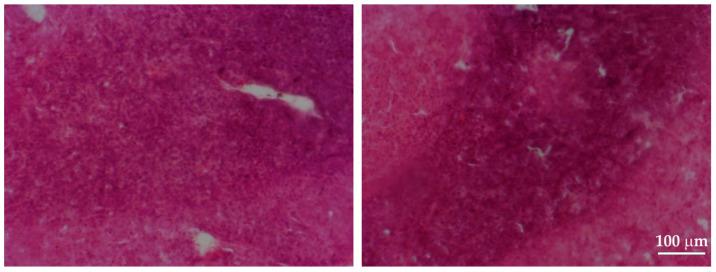

The HIFU ablation technique is limited by the long duration of the procedure, which results from the large difference between the size of the HIFU beam's focus and the tumor size. Ablation of large tumors requires treating them with a sequence of single HIFU beams, with a specific time interval in-between. The aim of this study was to evaluate the biological effects induced in a malignant solid tumor of the rat mammary gland, implanted in adult Wistar rats, during HIFU treatment according to a new ablation plan which allowed researchers to significantly shorten the duration of the procedure. We used a custom, automated, ultrasound imaging-guided HIFU ablation device. Tumors with a 1 mm thickness margin of healthy tissue were subjected to HIFU. Three days later, the animals were sacrificed, and the HIFU-treated tissues were harvested. The biological effects were studied, employing morphological, histological, immunohistochemical, and ultrastructural techniques. Massive cell death, hemorrhages, tissue loss, influx of immune cells, and induction of pro-inflammatory cytokines were observed in the HIFU-treated tumors. No damage to healthy tissues was observed in the area surrounding the safety margin. These results confirmed the efficacy of the proposed shortened duration of the HIFU ablation procedure and its potential for the treatment of solid tumors.

高强度聚焦超声(HIFU)消融技术受到手术时间长的限制,这是由于HIFU束焦点大小与肿瘤大小之间存在较大差异所致。消融大肿瘤需要用一系列单个HIFU束对其进行治疗,且其间要有特定的时间间隔。本研究的目的是根据一种新的消融方案,评估在成年Wistar大鼠体内植入的大鼠乳腺恶性实体瘤在HIFU治疗期间所诱导的生物学效应,该方案使研究人员能够显著缩短手术时间。我们使用了一种定制的、自动化的、超声成像引导的HIFU消融设备。对具有1毫米健康组织边缘厚度的肿瘤进行HIFU治疗。三天后,处死动物并收集经HIFU治疗的组织。采用形态学、组织学、免疫组织化学和超微结构技术研究生物学效应。在经HIFU治疗的肿瘤中观察到大量细胞死亡、出血、组织损失、免疫细胞浸润以及促炎细胞因子的诱导。在安全边缘周围区域未观察到对健康组织的损伤。这些结果证实了所提出的缩短HIFU消融手术时间方案的有效性及其治疗实体瘤的潜力。